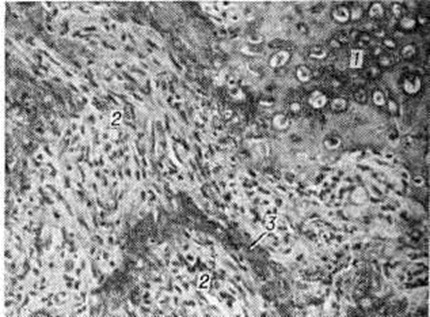

Рис. 3.

Микропрепарат кости при фиброзно-хрящевой остеодисплазии: 1 — хрящевая ткань; 2 — клеточно-волокнистая остеогенная ткань; 3 — незрелая костная балка; окраска гематоксилин-эозином; × 120.

Смешанная фибрознохрящевая дисплазия. Наличие в костях, поражённых фиброзной Остеодисплазия, крупных участков хрящевой ткани (рисунок 3) даёт основания для выделения самостоятельной формы — фиброзно-хрящевой дисплазии. Клинические Картина в основном сходна с таковой при фиброзной остео дисплазии. В отдельных случаях наблюдается сочетание фиброзно-хрящевой дисплазии с синдромом Олбрайта (смотри полный свод знаний Лайтвуда—Олбрайта синдром). Рентгенологические картина при смешанной фиброзно-хрящевой дисплазии характеризуется деформацией костей (искривления и утолщения, нередко выраженные выбухания за счёт центрально и периферически расположенных патологический очагов). В очагах на фоне различной величины участков разрежения выявляются участки крапчатого и пятнистого обызвествления. Густота расположения очагов различная — от отдельных разбросанных очагов до массивных конгломератов. Корковый слой на уровне локализации патологический изменений истончается и иногда едва дифференцируется.

В отличие от истинной фиброзной дисплазии при смешанной форме фиброзно-хрящевой дисплазии патологический очаги захватывают не только диафизы и метадиафизы, но и метаэпифизарные отделы костей. Наряду с трубчатыми поражаются плоские, губчатые и короткие трубчатые кости (рисунок 4 и 5, а, б).